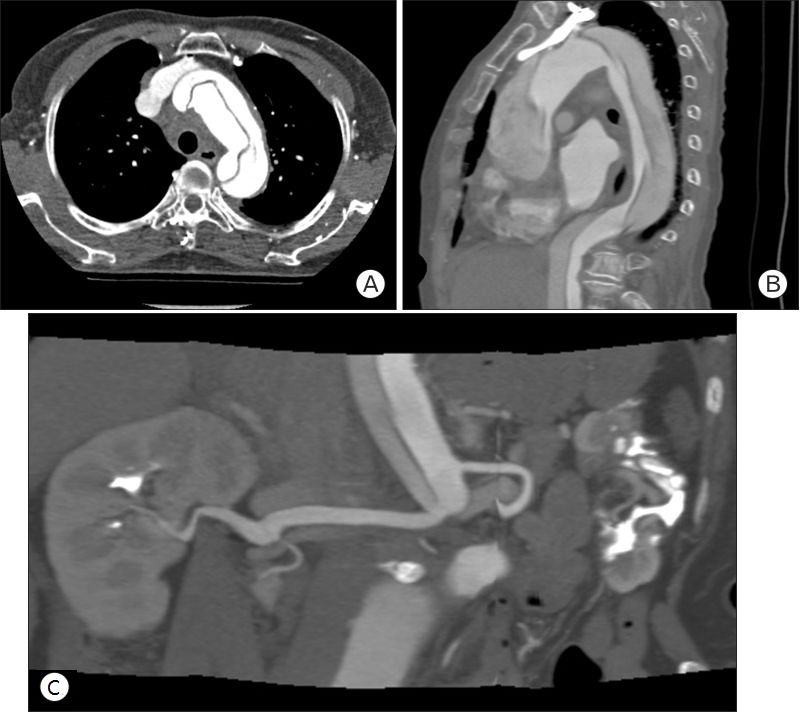

心电图提示:窦性心律,非特异性ST段改变。心肌酶、TnI水平均为正常,D-二聚体升高(13.60 ug/mL),其他实验室检查未见明显异常。急诊医生考虑胸痛原因不太可能是ACS,进行了胸片(图1)及CT检查(图2)。

图1 胸片提示纵膈轻度增宽

图2 CT检查提示A型主动脉夹层(A, B)远端靠近右侧肾动脉主干

没有冠脉介入治疗的指征,立即联系胸外科进行紧急手术。术后患者出现房颤,连续泵入胺碘酮治疗后得以控制。术后18天患者出院,恢复良好。